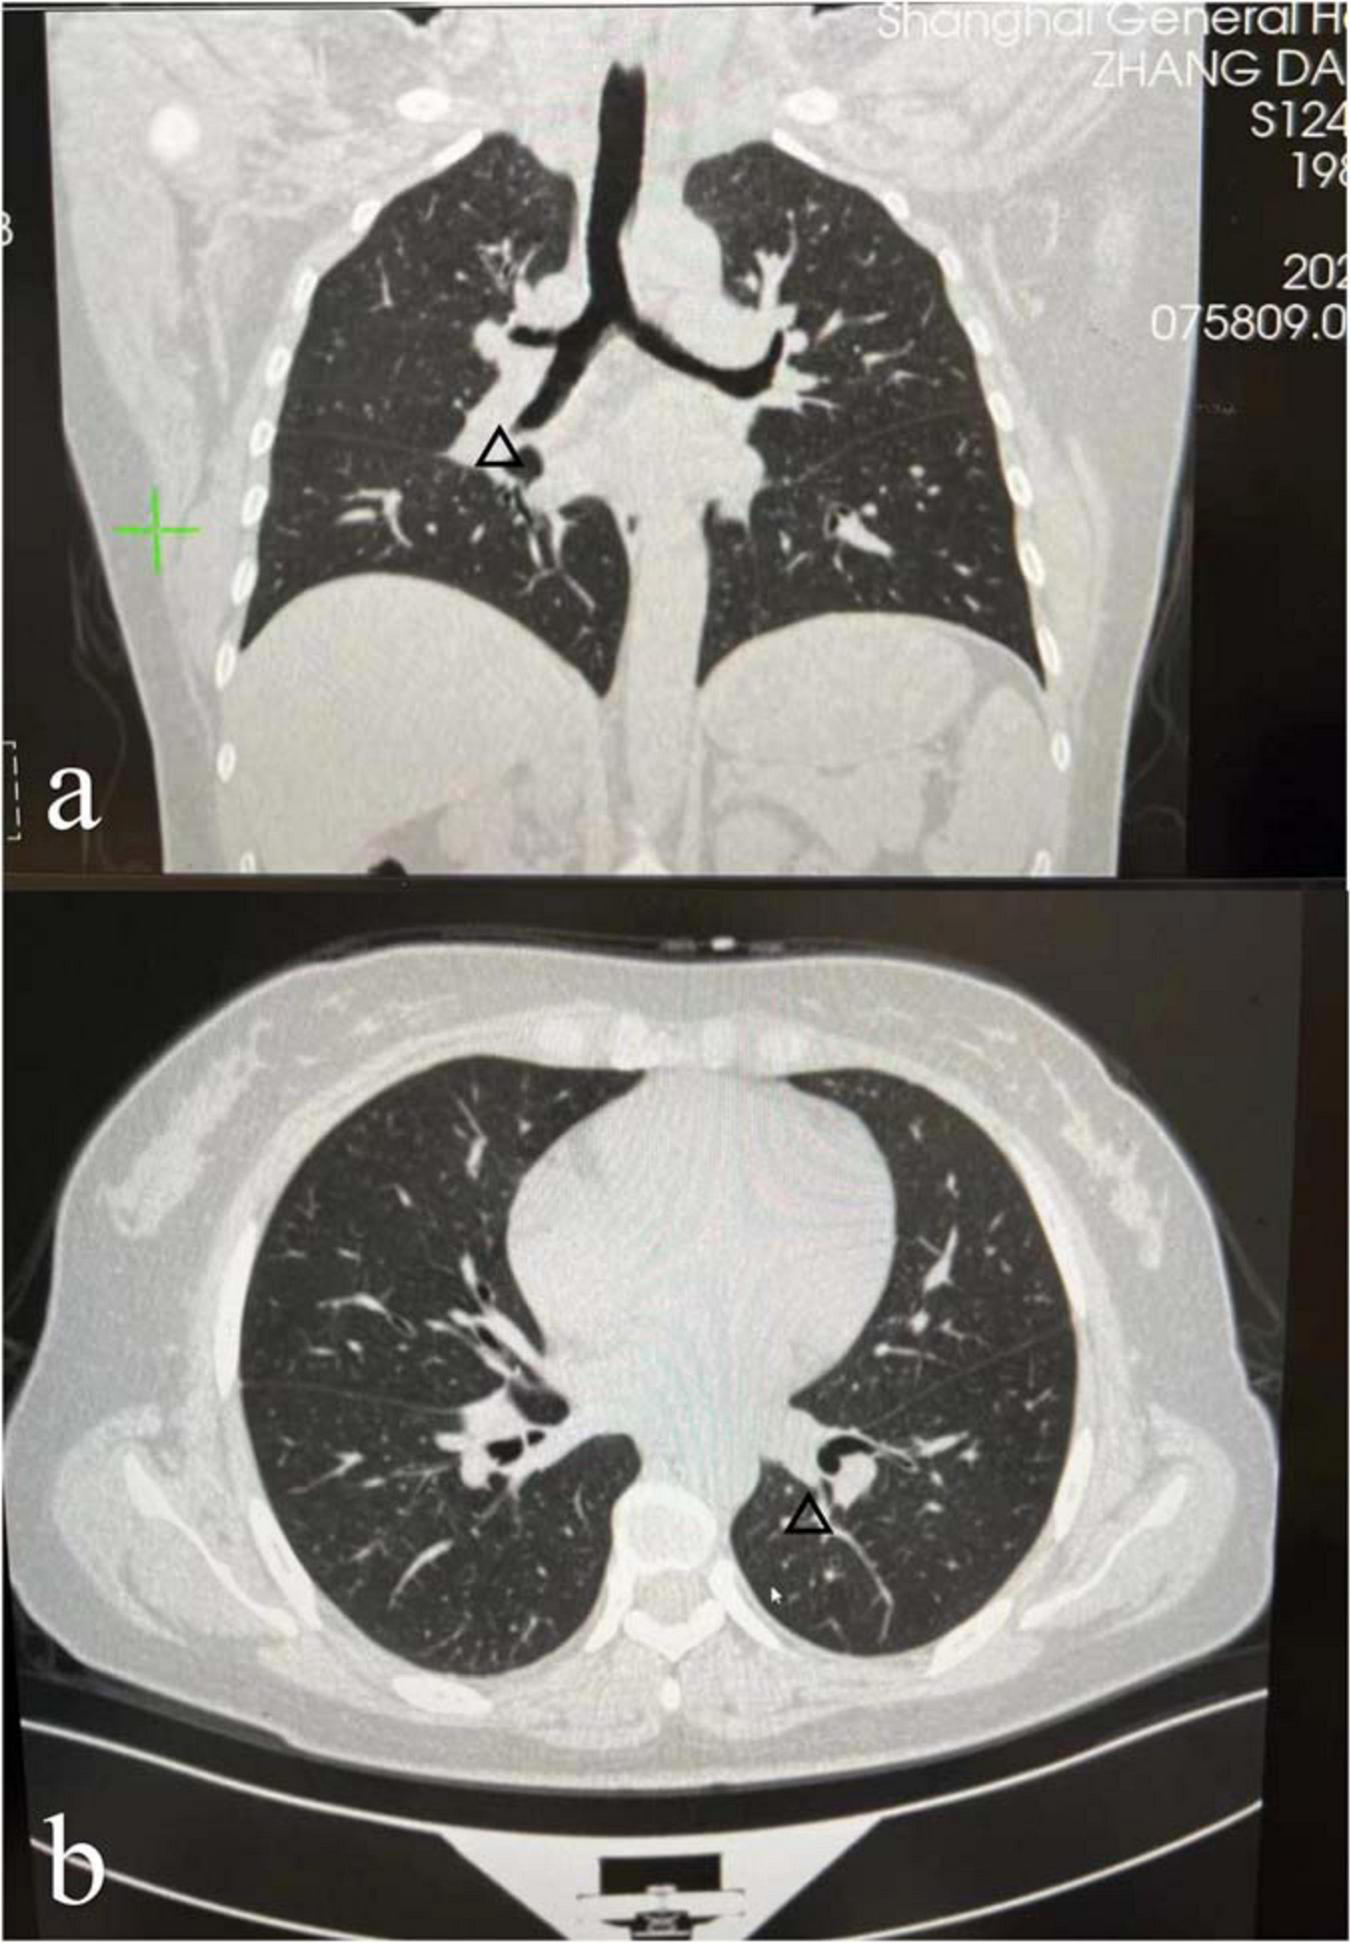

The results of laboratory tests such as serum angiotensin-converting enzyme (ACE) levels and T-spot were within normal limits (Table 1). Enhanced computed tomography (CT) of the chest with contrast demonstrated a few diffuse reticulonodular opacities in the bilateral lower lobe, bilateral hilar lymph nodes enlargement, and in the posterior segment of the right upper lobe are some small ground glass nodules (Figures 2a,b). The patient declined additional invasive diagnostic procedures, such as bronchoscopy/BAL or EBUS for lymphadenopathy.

FIGURE 2

Enhanced computed tomography (CT) of the chest with contrast demonstrated a few diffuse reticulonodular opacities in the bilateral lower lobe, bilateral hilar lymph nodes enlargement [the arrows in panels (a,b)], and in the posterior segment of the right upper lobe are some small ground glass nodules.